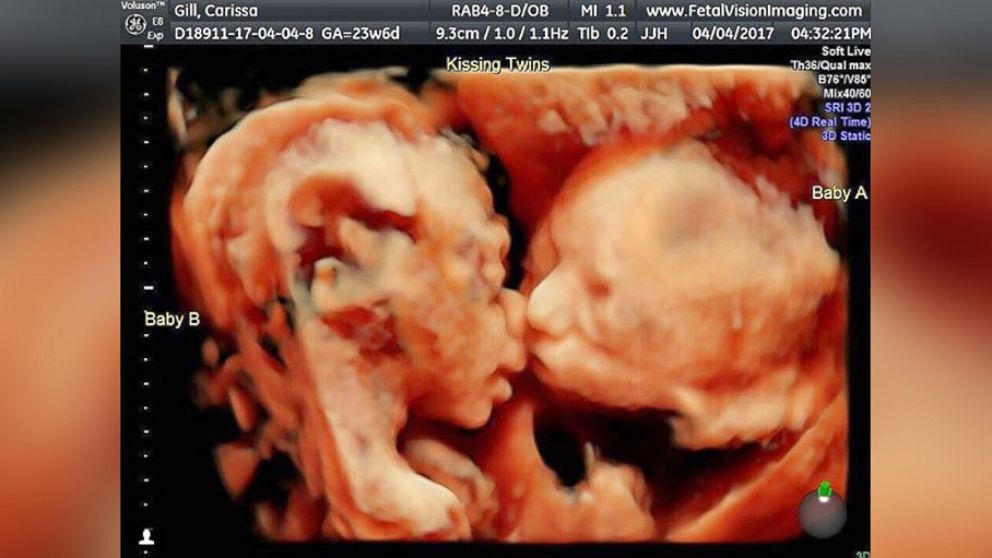

Badanie ultrasonograficzne to dla rodziców jedno z najważniejszych badań prenatalnych, ponieważ w łatwy sposób można podejrzeć rozwijający się płód, jego płeć oraz stan zdrowia. Ponadto wykonane w technologii 4D pozwala obserwować go w czasie rzeczywistym. W przypadku tych bliźniaczek stało się to dodatkowym atutem, ponieważ dziewczynki podczas badania postanowiły skraść sobie całusa.

Kiedy Carissa Gill była w 24. tygodniu ciąży postanowiła wykonać badanie USG 4D. Jest to USG trójwymiarowe w czasie rzeczywistym, co oznacza możliwość obserwacji dziecka, jego położenia w łonie matki i reakcji, w danym momencie.

W tym celu udała się do Fetal Vision Imaging w Pensylwanii (Stany Zjednoczone). Jednak nie spodziewała się, że wynik badania będzie tak zaskakujący. Bliźniaczki były bowiem ułożone w dość nietypowy sposób.

- Na tradycyjnym USG nigdy nie były tak blisko siebie, a tu leżały twarzą w twarz – mówi Gill. – Mogłam obserwować, jak ruszają ustami, jak się kopią nawzajem, ale to, co się stało na końcu, bardzo mnie wzruszyło. Bella pocałowała Callie w policzek – dodaje.

Carissa i Randy nie byli w stanie uwierzyć, w to co widzą. Również lekarz wykonujący badanie był w szoku. Pierwszy raz widział coś takiego. Niezwykłe badanie zostało zarejestrowane i szybko podbiło serca internautów.